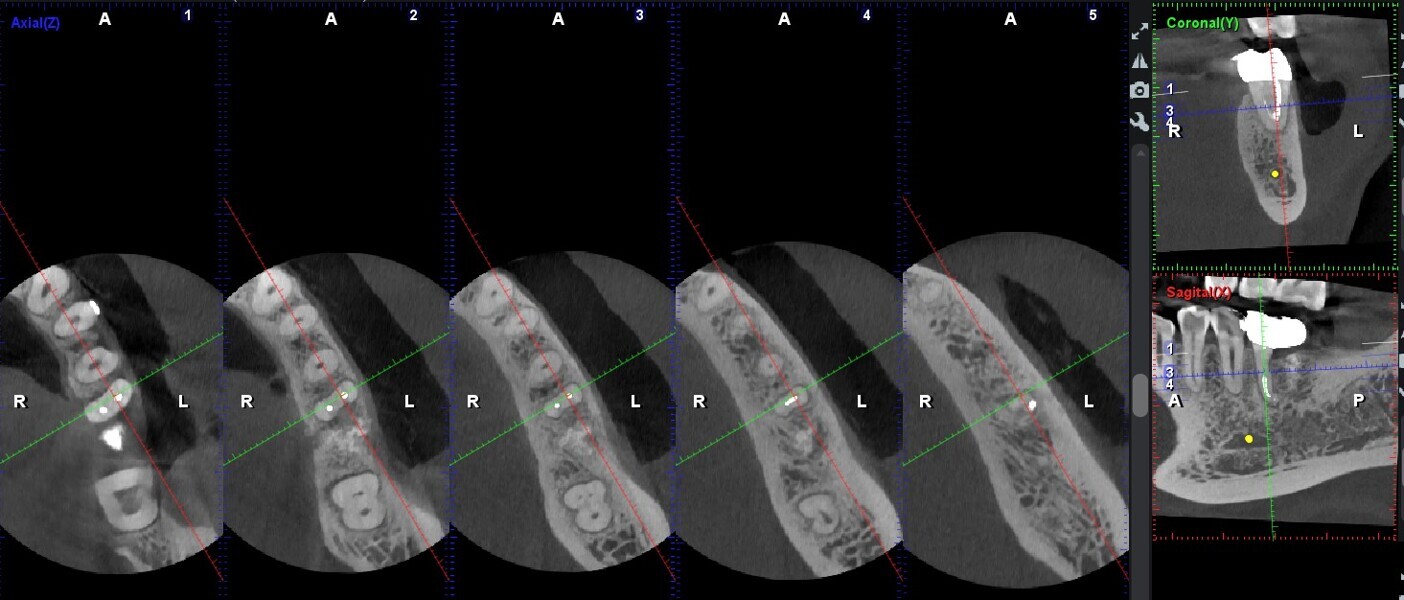

One year later, the restoration was performing well and the patient was asymptomatic. Radiographs and a CBCT control scan showed complete bone healing. On the periapical radiograph, the tooth showed a healthy periodontal ligament and no signs of failure in the restoration (Fig. 12). The cross-sectional, axial and coronal views of the CBCT scan showed good bone width and height and no pathological findings (Figs. 13–16). The oclusal scans and clinical images showed good adaptation of the new restoration and a healthy gingiva (Figs. 17–20).

Overall, the prognosis of these case reports varies greatly. For the hemisection scenario, Setzer et al. conclude in a meta-analysis of the literature that, based on proper case and patient selection, crown and root hemisection can be a good option for saving teeth, as it showed an overall cumulative survival rate of 85.6%, comparable with that of primary endodontic treatment (87%–97%), non-surgical retreatment (89%) and surgical retreatment (88%).8 They concluded that this may encourage dental clinicians to use these procedures to prolong the lifespan and save the natural dentition.8 We strongly believe in this as well, as our case is periodontally stable and has remained without any signs or symptoms of disease, confirmed radiographically and with CBCT analysis. However, at the three-year recall, the previous fixed prosthesis had debonded, and the area presented with gingival inflammation and marginal maladaptation. A decision was made to change the design to a CAD/CAM zirconia crown limited to the contours of the remaining tooth structure of the hemisected tooth.

Within the limitations of this case report, it is our opinion that, with proper case planning and patient selection, crown and root hemisection can be a valid option with a fairly good prognosis after a four-year follow-up. CBCT analysis showed a good healing pattern and ideal bone parameters for implant placement if needed in the future. It is important to state that the patient maintained good hygiene and attended regular periodontal control appointments every four to six months and was monitored radiographically, all of which we think has contributed to the outcome obtained.